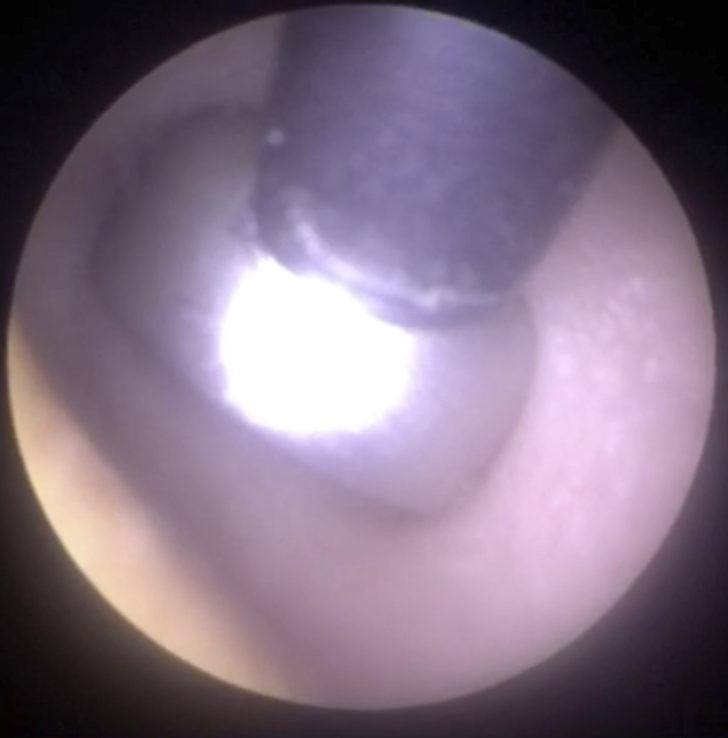

İşitme cihazı pilinin bulunduğu noktayı bir kamera yardımıyla teşhis eden Mr. Neel Raithatha, ardından mıknatısı pile yaklaştırdı.

Kısa süreli bir uğraş sonucu pili kulak kanalından güvenle çıkarmayı başardı.